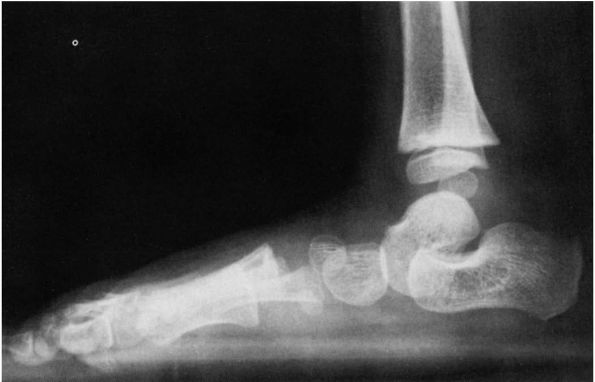

![]() |

FIGURE 20-9. Hypermobile flatfoot associated with short Achilles tendon. (A) Standing lateral radiographs reveal talus in plantar flexion, calcaneus in equinus indicative of contracted Achilles tendon. (B)

Forced plantar flexion lateral radiograph. The forefoot is collinear with the longitudinal axis of the talus, indicative of passive correctability of this deformity. The patient’s condition resolved with Achilles tendon lengthening. |